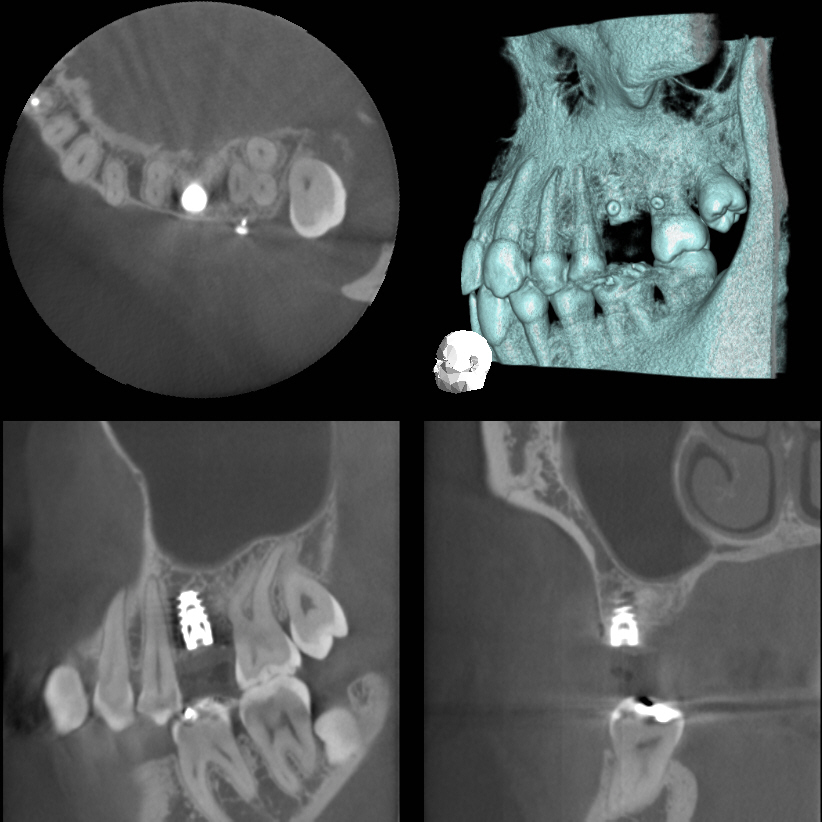

ソーセージテクニックは難しいといわれている垂直的に骨造成をするテクニック。先端美容テクニックといえます。3DX画像 患者様の状態・ご希望 上あごの奥歯が長いこと痛みが取れません。前医では歯が破折している可能性があるといわれました。ブリッジにはしたくありません。ササオインプラントセンターでCTをお…